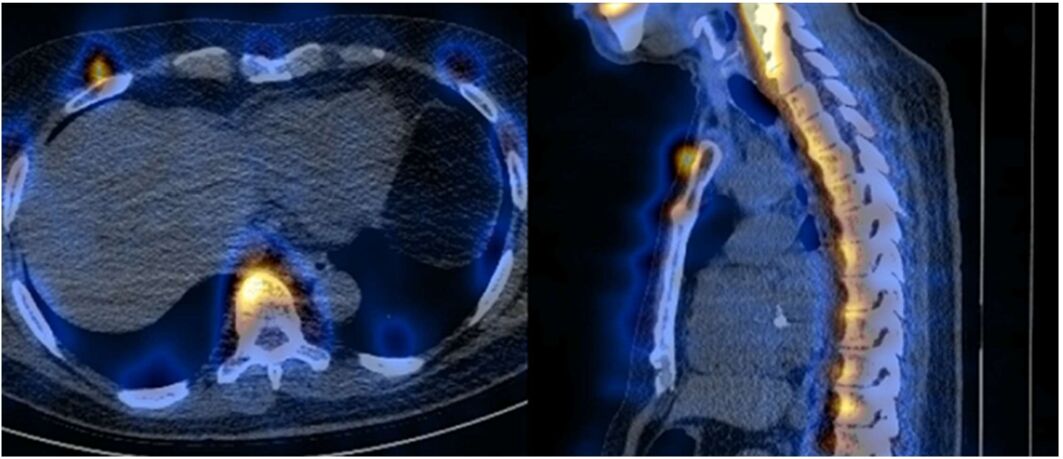

72.以SPECT/CT進行骨骼斷層掃描,融合的影像如圖所示,其假影最可能的成因為何?(A)misregistration(misalignment) (B)metal artifact (C)uniformity artifact (D)truncated artifact